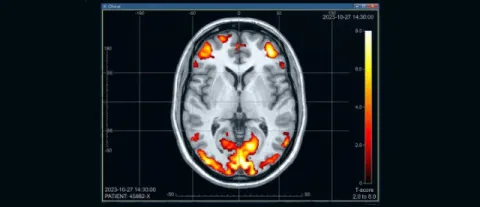

Effetti collaterali dei comuni psicofarmaci

Il TSO: Trattamento Sanitario Obbligatorio